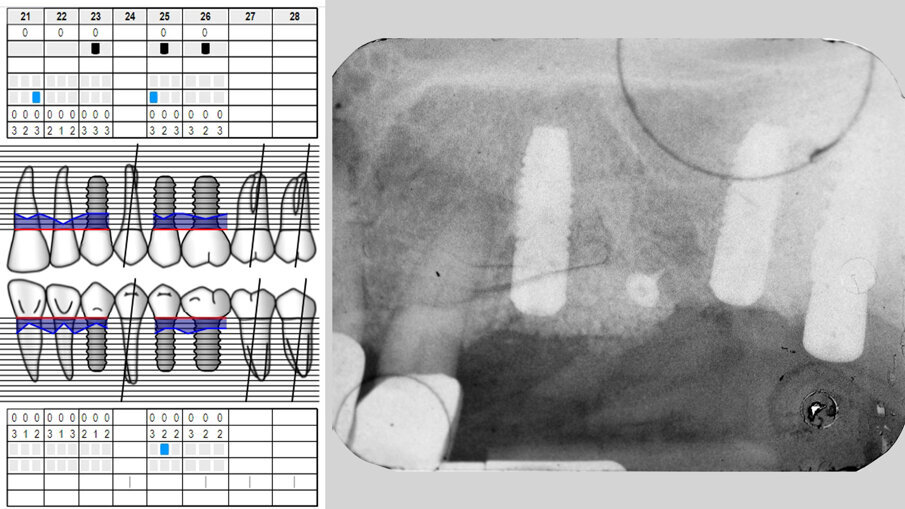

Paziente di aa 55, femmina, viene riferita per una sospetta peri-implantite in corrispondenza dell’impianto osteointegrato in zona 2.3; all’esame rx endorale e al sondaggio peri-implantare si evidenzia un riassorbimento osseo che interessa prevalentemente l’aspetto buccale: viene pertanto confermata la diagnosi di peri-implantite (Figg. 1, 2). Poiché l’esame radiografico endorale, a causa della sua natura bidimensionale, non sempre restituisce la reale morfologia del difetto osseo peri-implantare, è consigliabile incrociare i dati clinici, i valori del sondaggio e le immagini radiografiche raccolte al fine di evitare possibili errori diagnostici. Al momento della rivalutazione, sia lo stato dei tessuti molli peri-implantari che il livello di controllo di placca sono giudicati soddisfacenti e si programma un intervento di decontaminazione implantare associato a terapia rigenerativa del difetto intraosseo (G.B.R.) per mezzo di una membrana barriera di tipo riassorbibile sostenuta da un innesto osseo.

Fig. 1 - Sondaggio peri-implantare.

Fig. 2 - Esame RX endorale e sondaggio parodontale preperatorio.